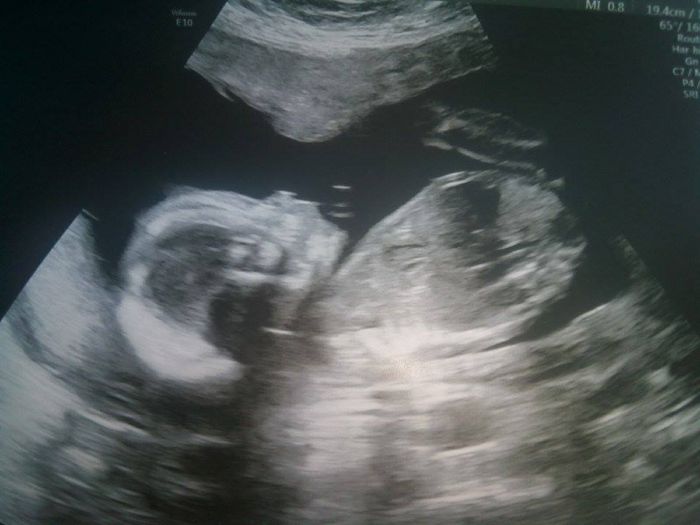

Ahoj holky :-) Jdu vas pozdravit a pochlubit se :-D Janči Eliška je užasná a Martas je pravý zlobišák :-D Ostatní holky mám na fb tak o nich vím -;))) jo pro ty na fb ...je to zatim celkem tajne tak na fb neprofláknout :-D Po 20 letech snahy jsem se dočkala a ČEKÁM KLUKA ! :-D 14.2.Na Valentyna jsme byli v Českých Budejovicich na genetice a vše ok a je to kluk :-))))) Termín mám 2.7. Pár foteček a já zas mažu :D Na jedné fotce jsou moje 4 holky ;-) Jsme všichni v šoku že do party přibyde kluk :-D Mějte se tu krásně :-) :-*